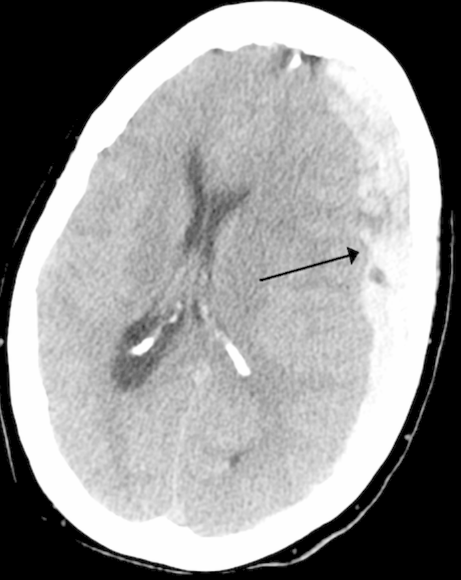

Which type of intracranial hemorrhage is seen in the image below? _____